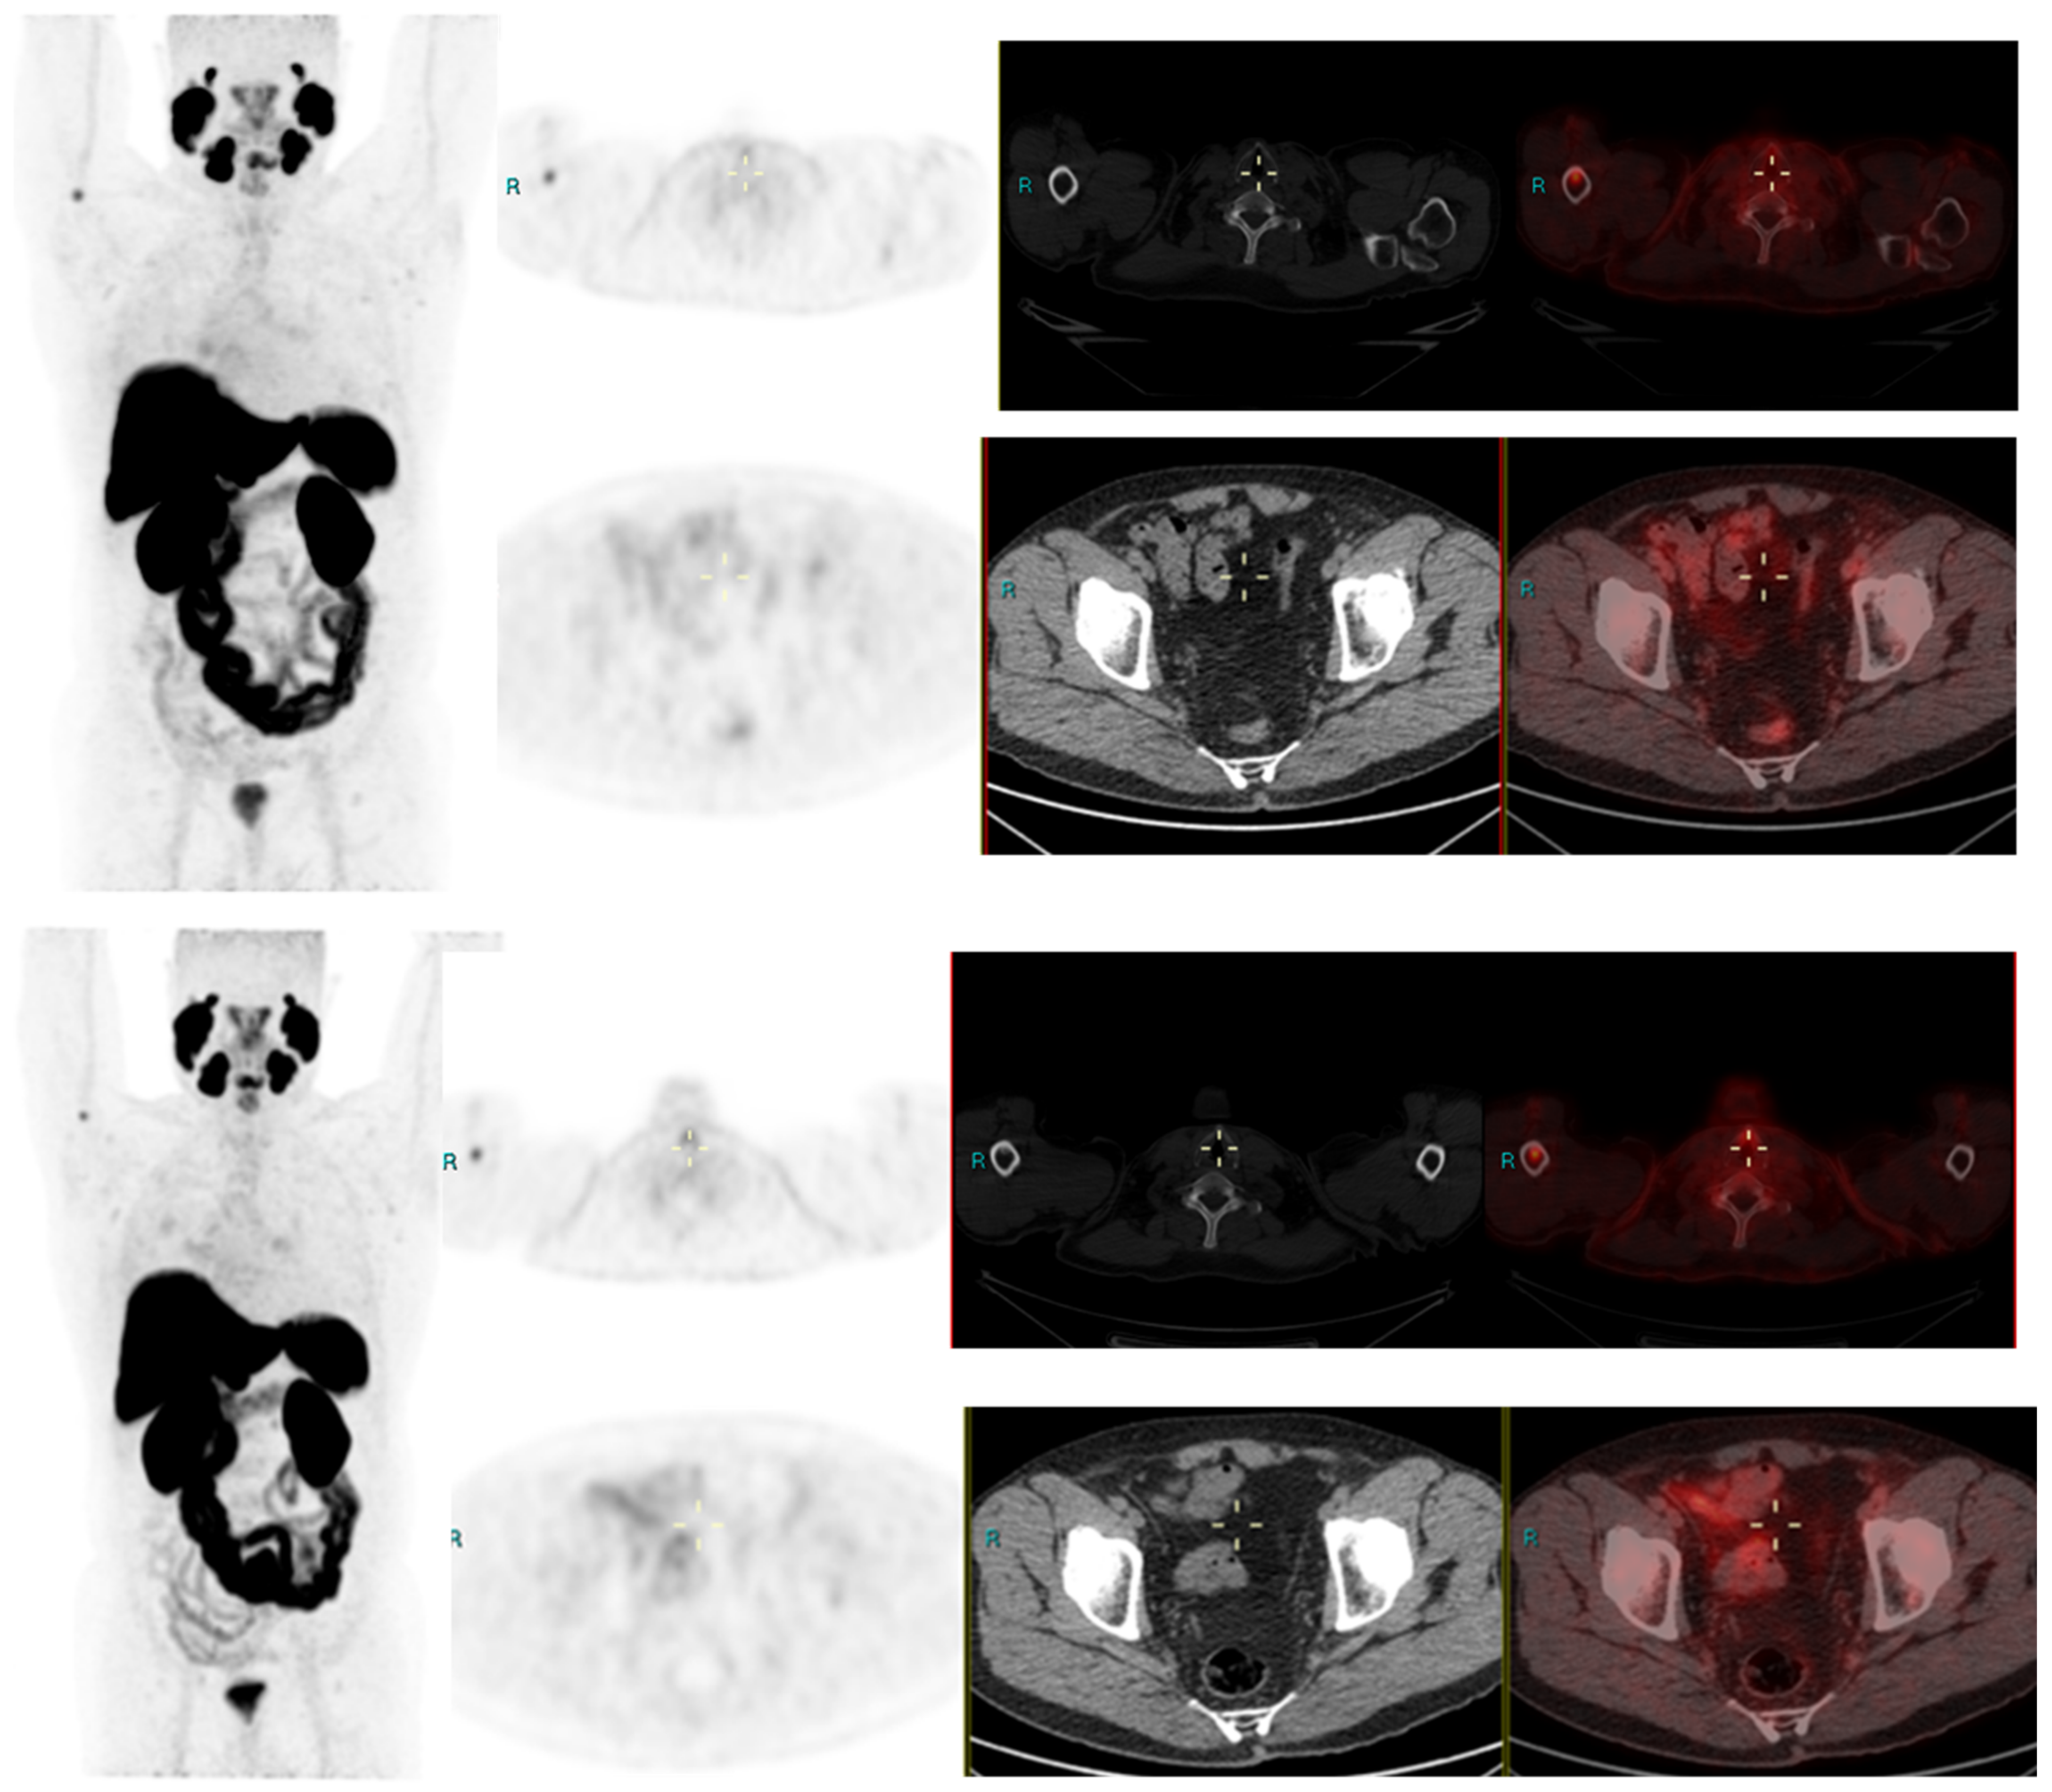

We conducted a separate subgroup analysis of 61 patients (Table 4) who had repeat imaging. Thirty had indeterminate findings on initial PSMA PET CT and the findings changed to a positive lesion in 14 (10 with known small indeterminate pelvic lymph node and four with known indeterminate prostate focus, PSA increase of 0.7 to 3.0 in 6 months), negative in eight (four with pelvic lymph node, four with uptake in bones on prior PET CT, PSA increase of 0.13–2). Six patient had the same indeterminate small pelvic lymph node, two had the same indeterminate retroperitoneal lymph node (PSA increase of 0.4 to 2.5). Overall, the follow-up PSMA PET CT was able to conclude in 24/30 patients on follow-up. Of the 31 patients who had repeat PSMA PET CT scans done for a further rise in PSA levels (PSA rise range 0.3–10), 24 had new lesions (prostate lesion in four, prostate and seminal vesicle involvement in four, pelvic/retroperitoneal lymph nodes in 12, new bone lesion in four) and eight had negative scans even on repeat imaging (PSA rise 0.3–2.3). For example, patient in Figure 2 had negative scan at PSA of 3.4 ng/mL, PSA velocity of 1.3 ng/mL in six months. The uptake in right humerus is at the site of known prior humerus fracture and therefore it was categorized as PSMA RADS 1 B (7). Another patient in Figure 3 had and indeterminate lymph node at PSA 6.5 ng/mL, after rise of 3 ng/mL in 2 years, it was categorized as RADS 3A(7). An interesting finding in this case was the consolidation changes in the right upper lobe, which resolved in a follow-up CT performed after 2 months (Figure 4).

Figure 4.

PSA 0.9 ng/mL. Positive lymph node metastasis and suspicious uptake in prostate.